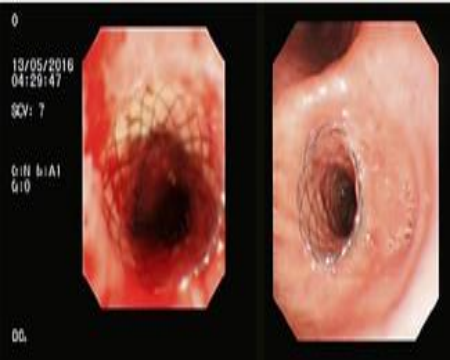

科室已在支气管镜下介入治疗方面取得飞越的进步,如开展了高频电刀、激光、微波、氩气刀、冷冻、支气管球囊扩张术、气管内肿瘤切除术、支架置入、超声引导下经支气管镜针吸活检术(EBUS-TBNA)等;同时开展内科胸腔镜检查;2020年我科成功完成首例气管镜下单向活瓣植入治疗气管胸膜瘘,并取得良好的效果。经支气管镜介入治疗取得了很大进步,在治疗气管支气管肿瘤、气管支气管腔内良性病变方面的效果肯定,免除了部分患者开胸手术的痛苦以及手术带来的肺功能损失等并发症。